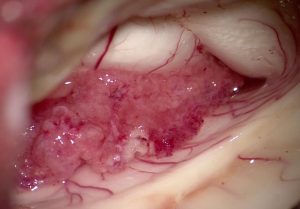

脈絡叢のビデオ2分(ここをクリック)

形や色や脳室壁への付着,動静脈の流入出など詳しくわかります)